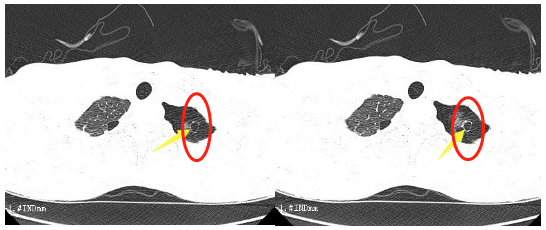

这段时间,16岁的小王突然出现了胸闷的症状,持续一周都不见好转。到我院胸心外科检查后,胸片提示左侧液气胸,积气为主,结合患者术前CT检查情况,考虑为肺大泡破裂引起的气胸。

患者肺大泡明显,术后切口较小。